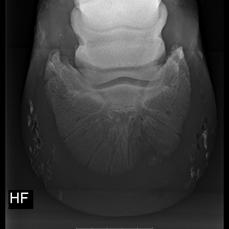

Silvas hov operation (keratom) - Røtgenbillede af keratomet (hornsøjlen) billede 2